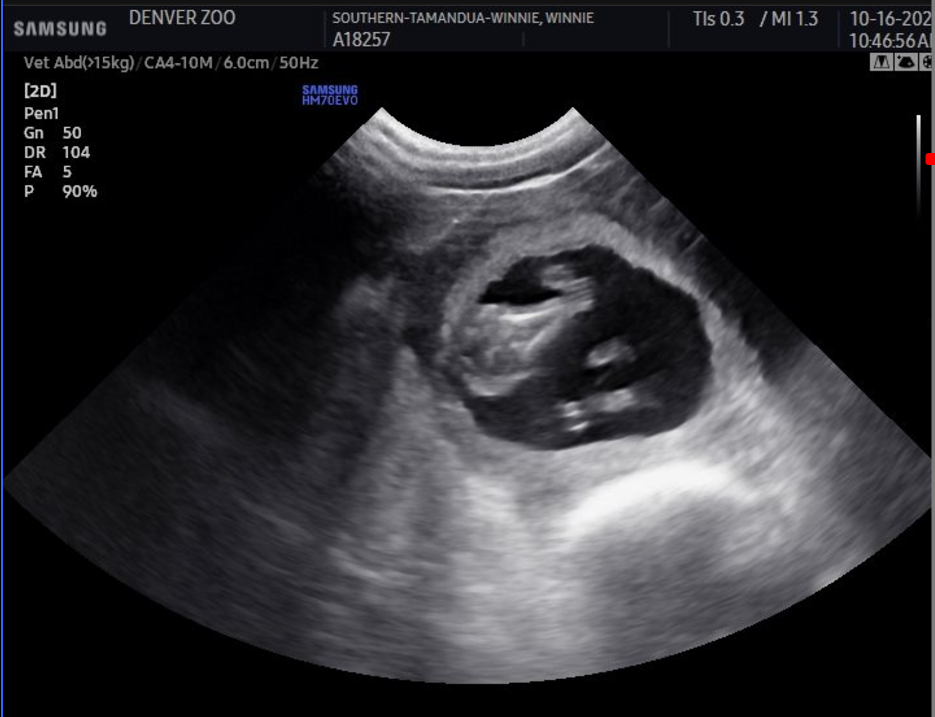

It might seem like a strange pregnancy craving, but Winnie is a tamandua (aka an anteater), after all. Winnie chows down, unconcernedly splattering avocado everywhere as veterinarian Kiran Fong and registered veterinary technician Danielle Coffman perform the ultrasound, capturing images and measurements of Winnie’s baby, which will be the first tamandua born at the Denver Zoo Conservation Alliance in over a decade.

While the weekly ultrasounds cannot confirm the sex of the baby, Wanner says that it will be born sometime in January. “Tamandua pregnancies are 130 to 150 days,” she says. “We’re doing a guesstimate window based on measurements Kiran is taking. Those measurements are actually really well-documented in scientific papers for gestational size in tamanduas. Because we were doing practice ultrasounds prior to the baby actually being here, Kiran and I were able to see it when it was just a tiny blip on the radar, so we have a good guess based on when we started seeing something that we can do the math on.” And yes, you can see the tamandua’s prominent snout in the ultrasound.